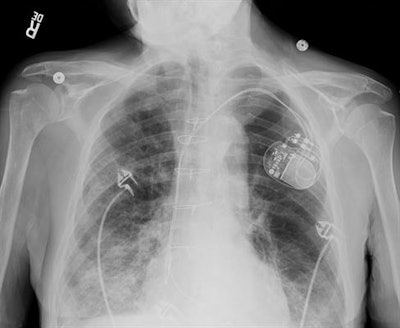

GE Healthcare developed its Discovery XR656 HD radiography system to reduce repeat imaging examinations. The unit includes FlashPad HD digital detectors, which have four times more pixels per area than previous technology, producing highly defined x-ray images, according to the company.

The firm's Helix image processing software enables workflow to continue smoothly, while the AutoRAD Suite supports the stitching of x-ray images. GE's Auto Image Paste tool supports seamless long-bone and spine x-ray studies.